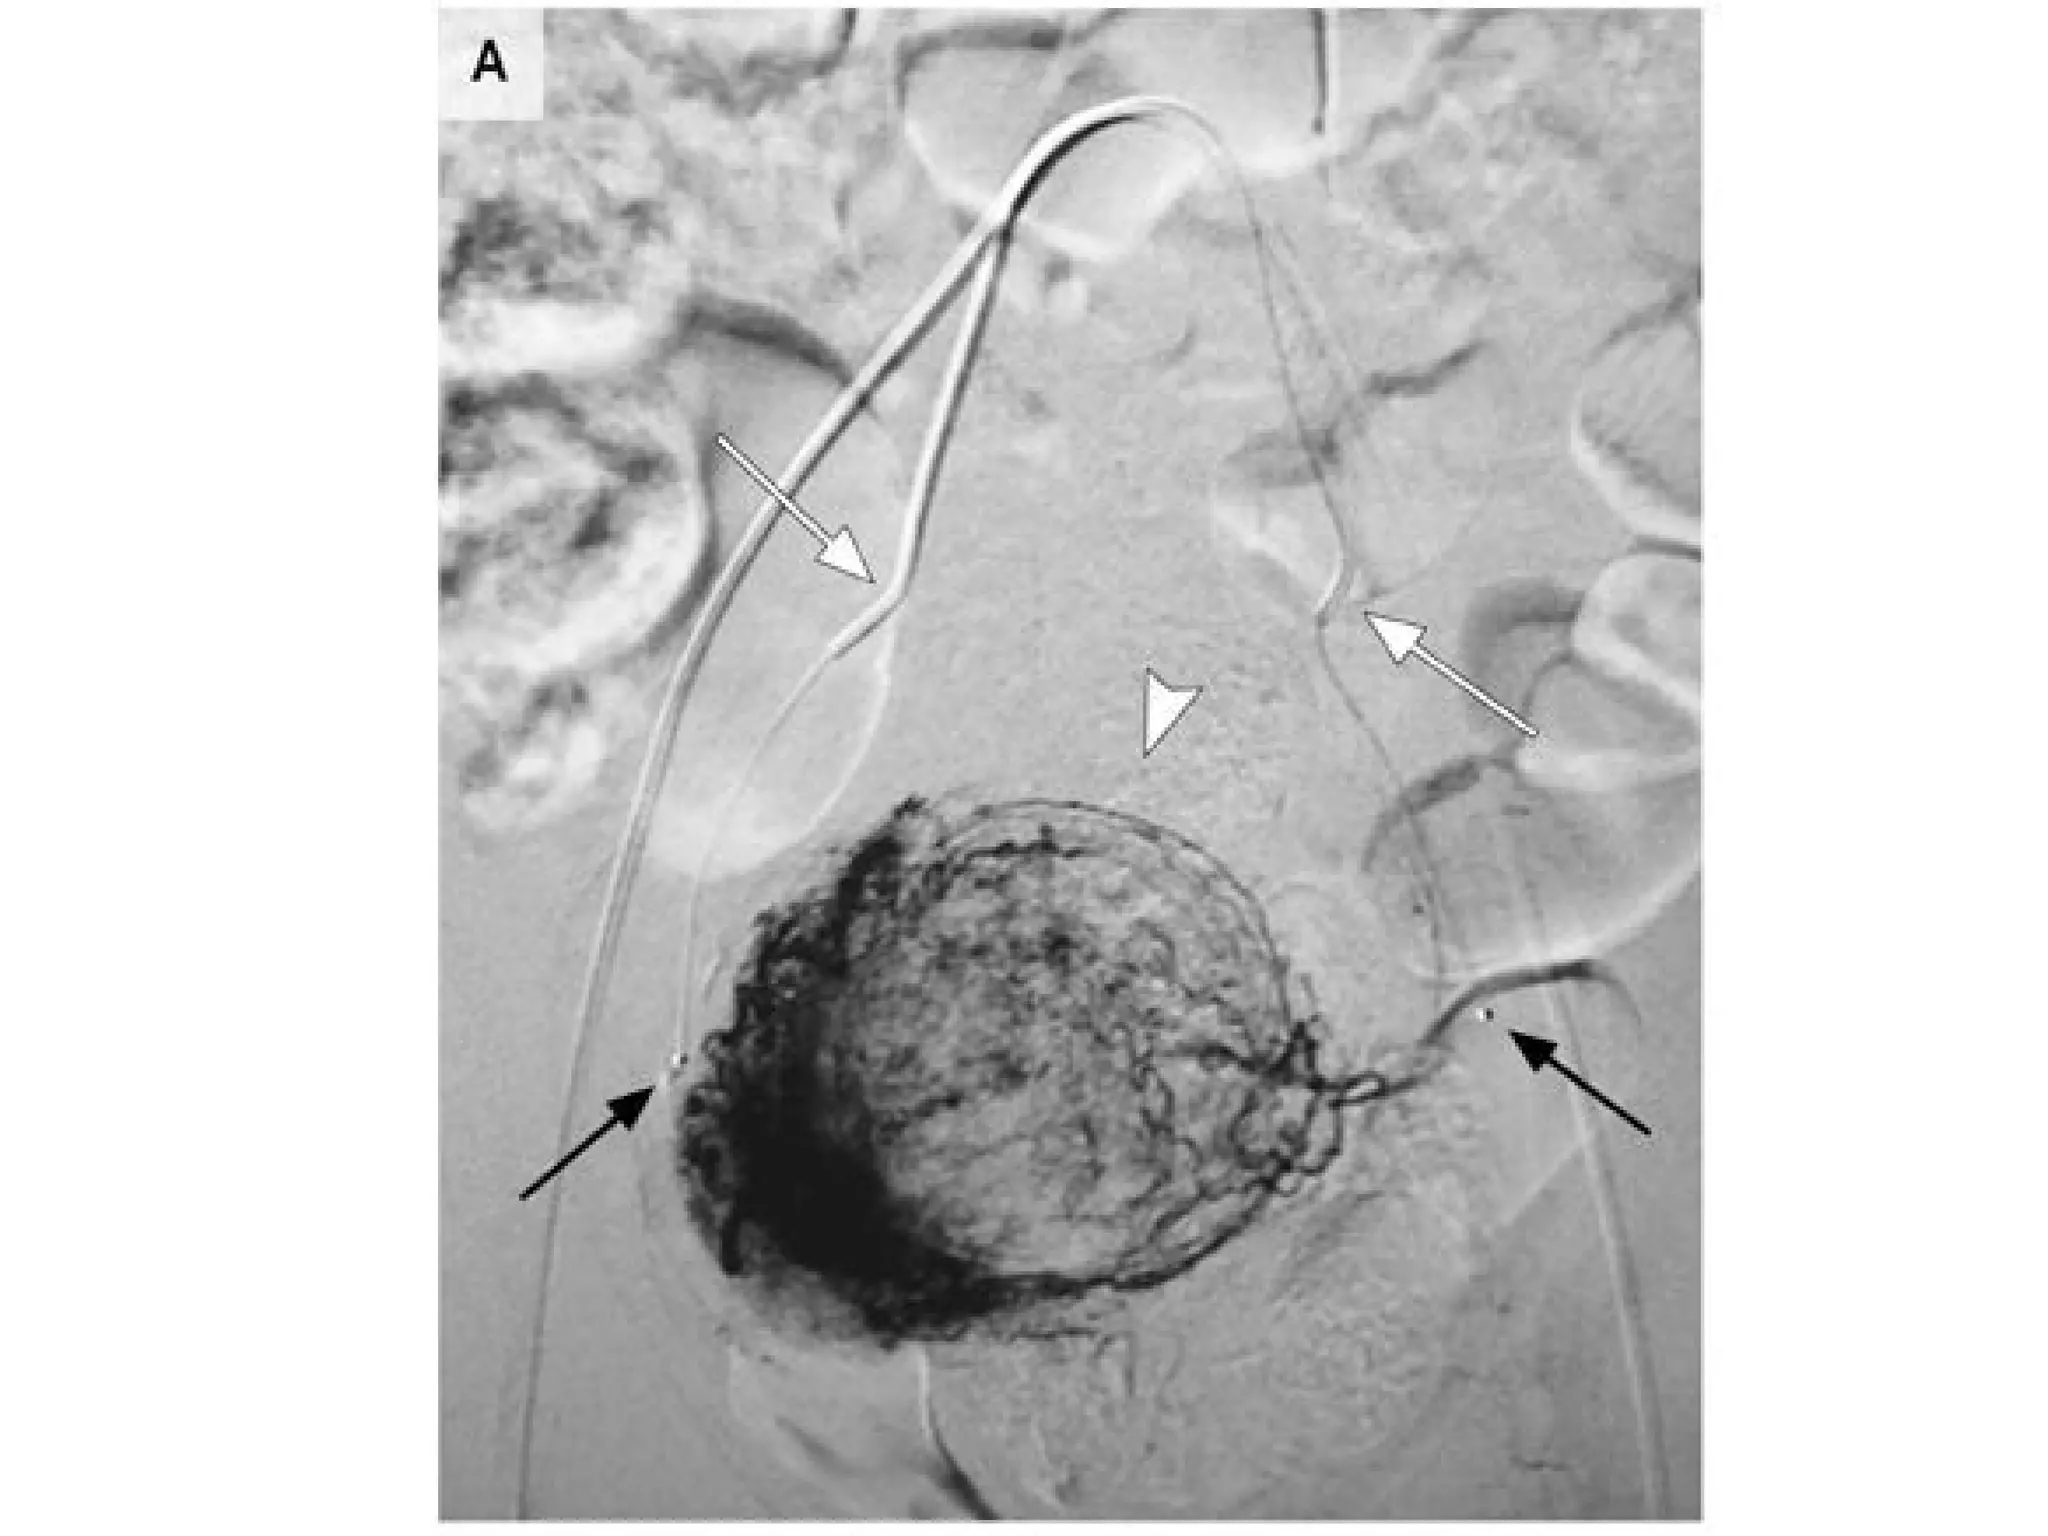

•Polyvinyl alcohol (PVA)

particles

•Trisacryl gelatin microspheres

•Gelatin sponge

•Preferential flow to fibroid

vessels

•Polyvinyl alcohol (PVA) particles •Trisacrylgelatin microspheres •Gelatin sponge •Preferential flow to fibroid vessels